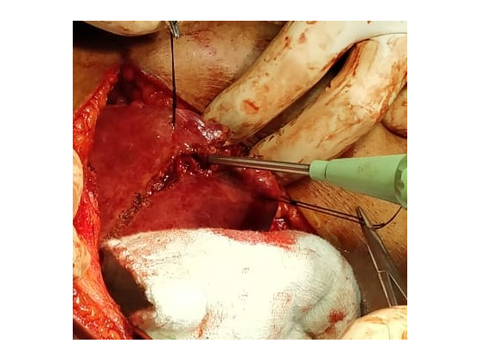

CAVITRON ULTRASONIC ASPIRATOR USED FOR LIVER RESECTION

LIVER RESECTION DONE USING CUSA